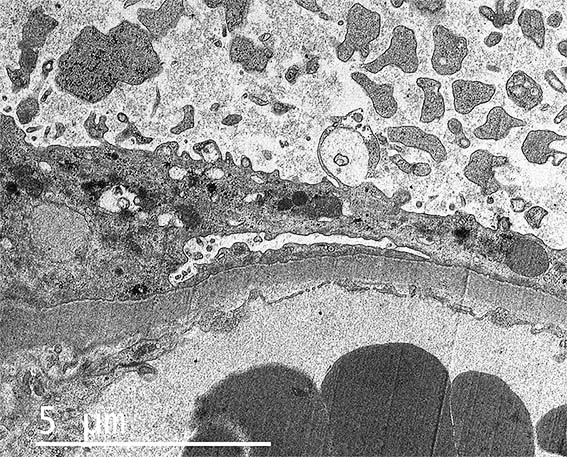

Figure 7. EM, original magnification, X4,500. How are the podocyte processes?.